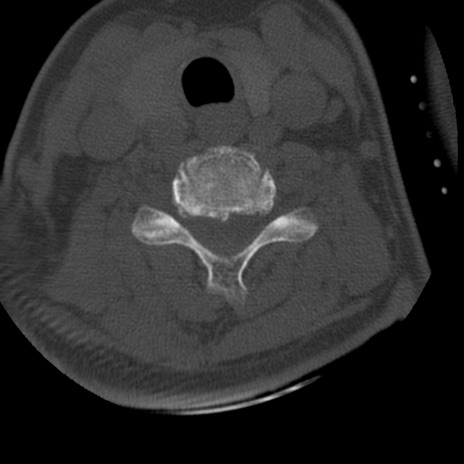

症例50 頚椎CT(横断像)

異常所見と診断は?

頚椎CT